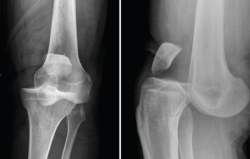

Radiología

El diagnóstico radiológico consiste en la realización de una radiografía sobre una zona del organismo para el estudio de los órganos que se encuentran en su interior.

La radiología es útil para el diagnóstico de las fracturas, luxaciones, osteoartritis o para cuantificar las desviaciones axiales y planificar las cirugías de realineación(1).

Es el procedimiento de imagen empleado generalmente como primera elección y es muy útil para la visualización de los elementos óseos, con la limitación que supone la superposición en un mismo plano de todas las estructuras atravesadas por los rayos X.

Deben hacerse proyecciones anteroposterior (AP) y lateral, generalmente con flexión de 30°, y axial de la rótula cuando se sospeche patología de esta; y proyecciones especiales oblicuas o laterales, proyecciones forzadas de varo o valgo, y AP en 45°, para valorar mejor la interlínea articular(2).

1. Lesiones traumáticas

1.1. Fracturas

1.2. Luxación femorotibial

La luxación traumática de rodilla es una entidad poco frecuente, que representa menos del 0,5% del total de las luxaciones articulares(3).

Requiere un tratamiento precoz, ya que una de sus complicaciones más graves es la lesión de la arteria poplítea, para cuyo diagnóstico se recomienda realizar un estudio de angio-TAC (Figura 4).

Figura 4. Radiografías anteroposterior y lateral de rodilla: luxación anterior de tibia y peroné.

2. Condrocalcinosis

El diagnóstico de los depósitos de pirofosfato de calcio se basa en el estudio radiológico, confirmado con la identificación de estos cristales en el estudio del líquido sinovial(4).

La radiografía es imprescindible en estos casos, pues la RM no los detecta (Figura 5).

3. Artrosis

La gonartrosis es la causa más frecuente del dolor de rodilla después de los 50 años. En la radiografía se observa una reducción de la interlínea femorotibial o femoropatelar, y una osteofitosis marginal (Figura 6).